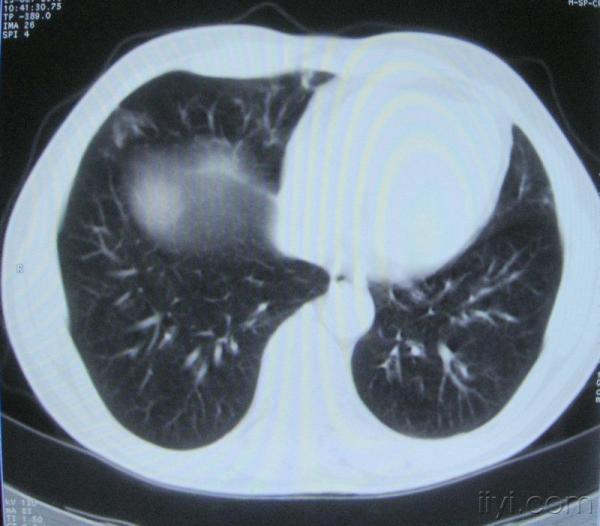

男。60岁,胸片示支气管炎治疗后复查CT。

你指那个肯定是淋巴结,中央系坏死,这很常见,特别在双侧腹股沟会经常看到。这个双侧腋窝及纵隔见多发小淋巴结征。

根据位置考虑应该是淋巴结,密度不均,是因为肿大的淋巴结中心液化坏死